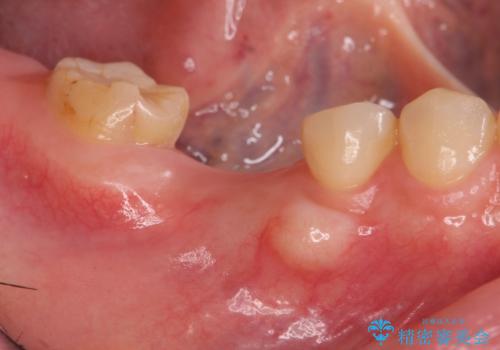

- 欠損し、放置していた奥歯に審美性に優れる入れ歯を作製したいと希望され来院されました。

ノンクラスプデンチャーは、入れ歯に通常ついている目立つ銀色のバネがないため審美性に優れる入れ歯です。